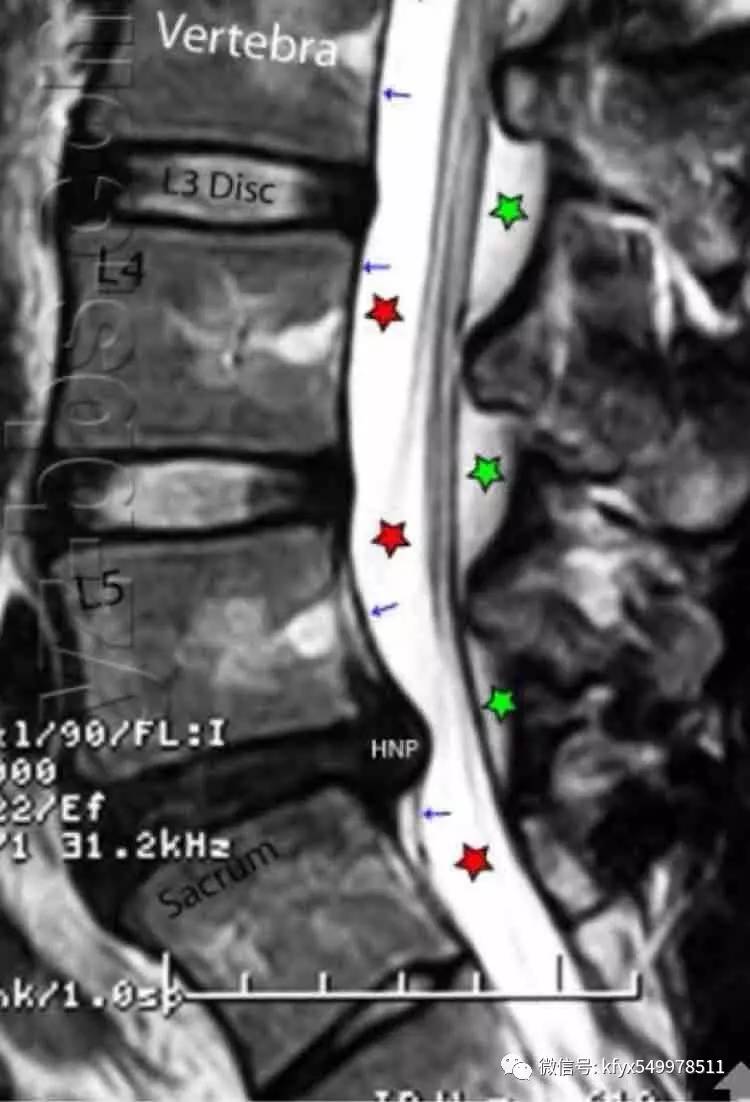

(2)椎间盘:腰椎椎间盘呈肾形,是由软骨终板、纤维环及髓核组成。软骨终板覆盖椎体上下面,在椎体与髓核之间。在SE席列T1加权像上,椎间盘中心部比周围部分信号强度略低,外周部分纤维环与前后纵韧带汇合处的信号更低。在T2加权像上信号强度恰好相反。纤维环和后纵韧带的信号相近,往往难以区分。髓核呈高信号。

髓核的水分含量随年龄增长而减少,在T1加权像上信号强度逐渐减弱。在30岁以上90%在T2,加权图像上椎间盘中央见一呈水平走向低信号呈夹心饼干样征象,属正常生理性老化退变。

(3)椎管内结构:①硬膜外间隙:硬膜外间隙系骨性椎管与硬脊膜之间的空隙,其内主要含脊神经、动脉、静脉、脂肪及少量结缔组织。腰椎的硬膜外间隙填充相当厚的硬膜外脂肪、韧带、神经和血管。硬膜外脂肪在T1及T2加权像上呈高信号强度。硬脊膜为致密纤维组织,在神经根平面外突,其内含有蛛网膜,共同构成神经根鞘。蛛网膜位于硬脊膜内面,二者之间有潜在的硬膜下隙。在MRI下,硬脊膜难与蛛网膜区分开,二者统称为鞘膜。②蛛网膜下隙:脊髓表面包绕软脊膜,软脊膜与蛛网膜之间为蛛网膜下隙。在MRI图像上见到的鞘膜囊内的脑脊液,实际是位于蛛网膜下隙的,脑脊液在T1加权图像上为低信号。在T2加权图像上信号高于脊髓。蛛网膜下隙在L2以下比较宽,由脑脊液填充,在T1加权像呈低信号强度,在L2加权像呈高信号强度,明显高于脊髓,因而脊髓结构可清晰显示。③脊髓马尾:脊髓位于蛛网膜下隙的中央.其末端为圆锥,圆锥的末端可在矢状面图像上清楚显示,止于L1,2平面。在T1加权像呈中等信号强度,在T2加权像信号强度比椎间盘和脑脊液低,为此二者易区分。脊髓的灰质与白质的MRI信号亦有不同,在横断面T1加权图像上,中央灰质是H形高信号,而周围白质信号较低。脊髓圆锥向下移行为纤维性终丝。终丝的信号强度类似或低于脊髓信号。约5%的正常人终丝内含有不同量的脂肪,信号明显增高。在圆锥平面向下走行的腰骶神经根称作马尾。马尾神经由上至下逐渐变少。旁正中矢状位显示神经根呈扇形从后上向前下方向延伸。④神经根的信号强度较低,但在脂肪组织的衬托下仍然十分清楚。静脉及静脉丛仍为低信号。大部分韧带为胶原纤维组织,在T1、T2加权图像上及部分翻转梯度回波图像上为低信号,黄韧带内含大量弹性纤维,故在T1 、T2加权图像上为中等强度信号。